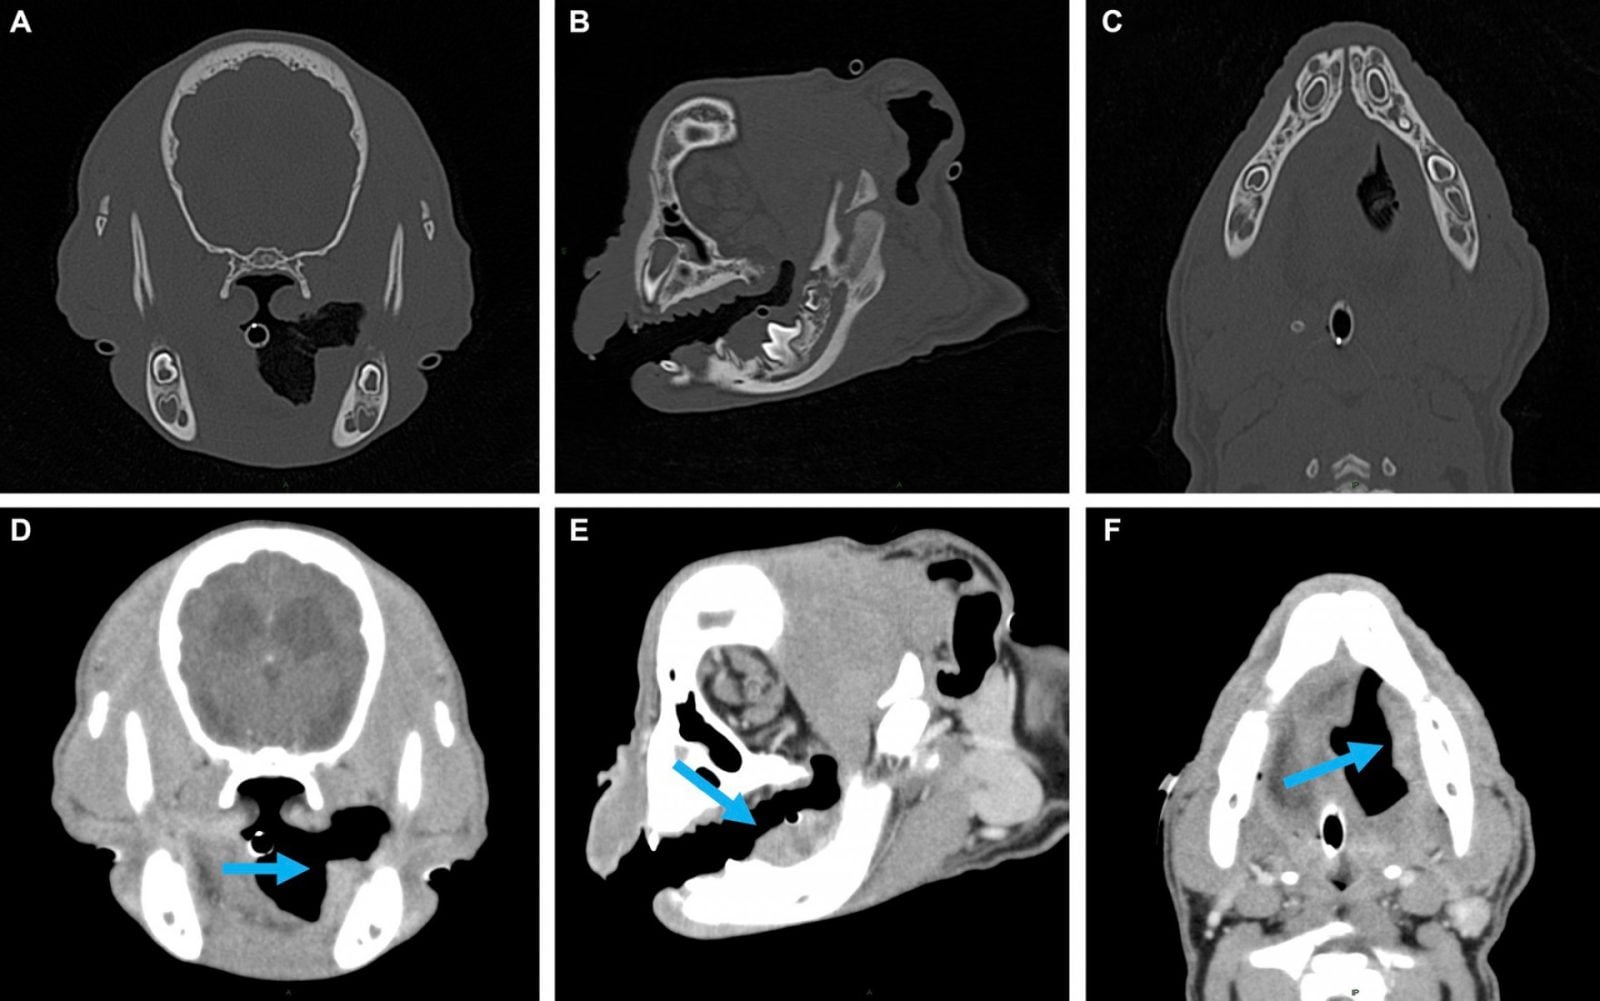

Tyson to 3-miesięczny buldog francuski, który zgłosił się z właścicielami na oddział Cornell University’s Dentistry and Oral Surgery Service w celu operacji rozszczepu podniebienia. Miał to być rutynowy zabieg, umożliwiający psu normalny rozwój. Niestety, podczas dokładnych badań, u zwierzęcia wykryto agresywny nowotwór szczęki – brodawkowatego raka płaskonabłonkowego pyska. Jest to drugi co do częstości występowania nowotwór złośliwy pyska u psów.

Diagnoza była jednoznaczna. By pies miał szanse na przeżycie, konieczne było usunięcie guza, a wraz z nim większości lewej żuchwy zwierzęcia. To oznaczało życie bez w pełni funkcjonującej szczęki i trudności praktycznie na każdym kroku – od przyjmowania posiłków, po interakcje z otoczeniem.

Przypadek opisany w czasopiśmie Frontiers in Veterinary Science jest niezwykły. Chociaż wcześniej zdarzały się niepotwierdzone przypadki regeneracji części żuchwy u młodych psów, u Tysona nie wydawało się to prawdopodobne ze względu na rozmiar usuniętej kości.

Weterynarzom udało się zachować duże ilości okostnej – cienkiej błony pokrywającej powierzchnie kości (także u ludzi). Okostna zawiera naczynia krwionośne i nerwy, które podtrzymują kość i są niezbędne do wzrostu pierwotnych szczęk. Bez niej regeneracja żuchwy nie byłaby możliwa. Nie bez znaczenia było także wykrycie guza u psa na tak wczesnym etapie, co podkreśla znaczenie odpowiedniej diagnostyki, także u zwierząt.

Nowa żuchwa Tysona jest prawie tak funkcjonalna jak “oryginał”, chociaż z technicznego punktu widzenia jest uważana za anormalną, gdyż jest pozbawiona niektórych cech, np. nie ma kanału żuchwy, w którym zwykle znajdują się naczynia krwionośne i nerwy. Choć zregenerowana szczęka jest tej samej długości, co część po prawej, nie ma zębów, z czym Tyson będzie musiał już zawsze żyć. W “nowej” kości nie ma śladów nowotworu.